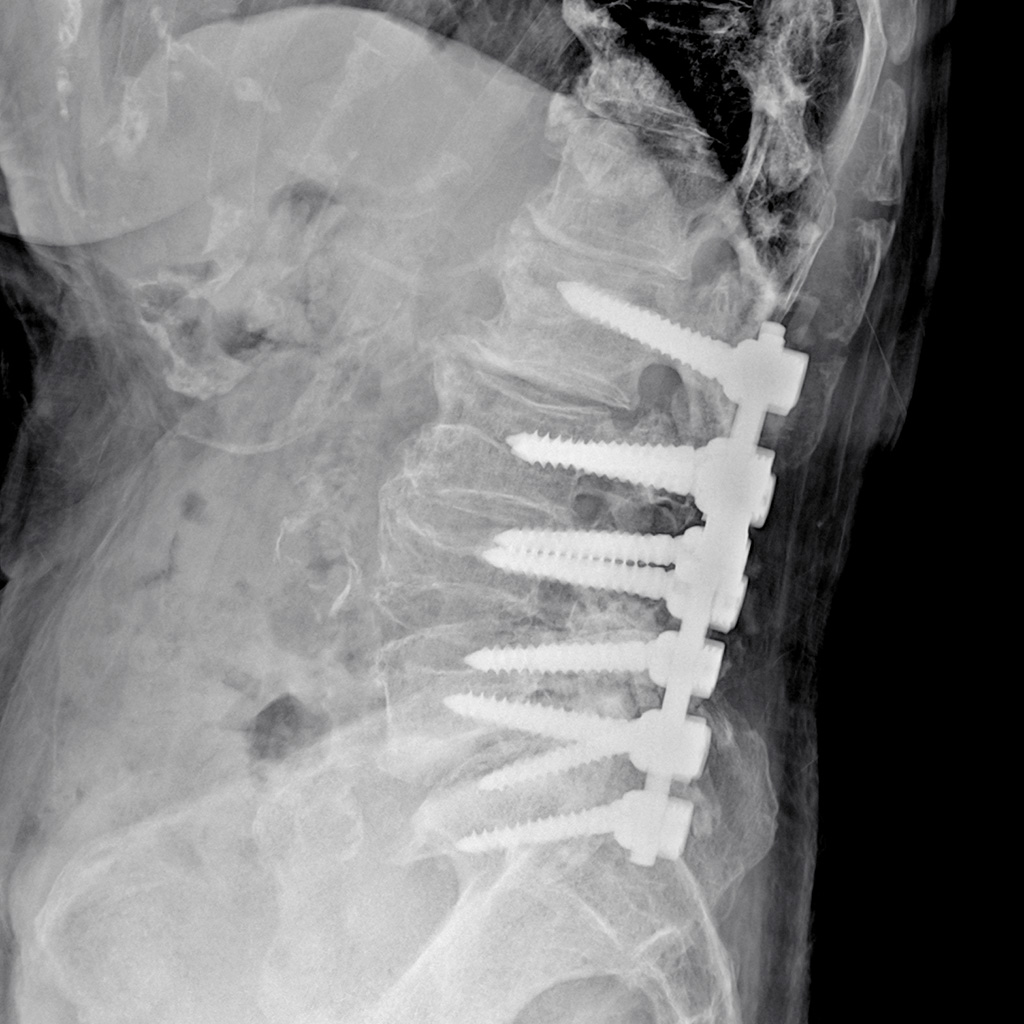

2.固定術(除圧 + 骨を固定する手術)

除圧に加えて、ずれた椎体を固定して安定性を確保します。

- 適応:不安定性が強い、除圧のみでは不十分

- 利点:腰椎の状態に合わせた細かい手術方法の選択が可能

椎体間固定術の種類と特徴

椎体間固定術は、椎間板のスペースにケージ(スペーサー)を挿入して椎間板の高さを回復し、椎間孔を間接的に広げる手術です。

- PLIF(後方腰椎椎体間固定術)

背中側からアプローチ。最も一般的な術式

- TLIF(経椎間孔的腰椎椎体間固定術)

背中側から片側アプローチ。神経への侵襲が少ない